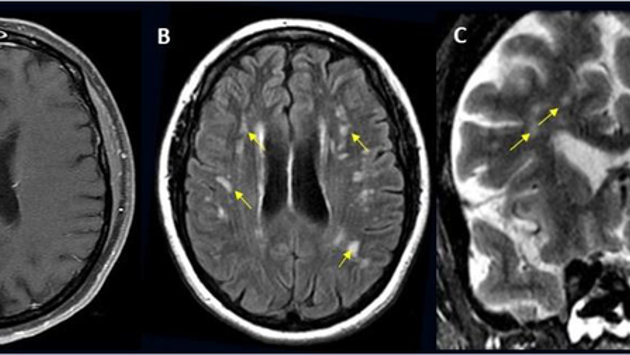

Потенциально смертельные поражения мозга встречаются у каждого сотого пациента, госпитализированного с COVID-19, выяснили неврологи из Университета Томаса Джефферсона. Подробнее об этом они рассказали на ежегодной встрече Радиологического общества Северной Америки. Авторы работы проанализировали почти 40 тыс. случаев госпитализации пациентов с COVID-19. Средний возраст больных составил 66 лет, мужчин среди них было вдвое больше, чем женщин. Самой распространенной причиной госпитализации была спутанность сознания и изменения психики, затем следовала лихорадка. Серьезные осложнения, затрагивающие мозг, развивались у 1,2% пациентов. Чаще всего это был ишемический инсульт, на втором месте по распространенности оказалось внутричерепное кровоизлияние, на третьем - воспаление мозга. Также исследователи наблюдали острый диссеминирующий энцефаломиелит, воспаление спинного мозга и прочие поражения нервной системы. Чтобы успешнее лечить пациентов, важно знать, насколько часто встречаются осложнения со стороны нервной системы, поясняют исследователи. Они предлагают чаще обследовать мозг пациентов с COVID-19, чтобы не упустить патологию, способную погубить жизнь больного.